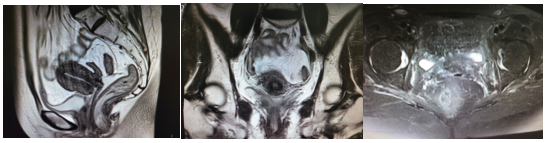

腔内近距离放疗选择CT引导下宫腔管联合插植针进行,将宫腔管按照宫腔方向插入5-6cm,然后平行于阴道方向围绕宫腔管均匀布置插植针,目的将全部宫颈和宫旁组织包括在靶区范围内,从而进行病灶局部加量。近距离放疗剂量3000cGy/5F,治疗之前给予患者预防性止血、止疼等对症治疗以减轻相关副反应。患者治疗结束后1个月复查核磁(图3):宫颈局部肿块基本消失,局部呈放疗后改变,盆腔少许积液。

近距离放疗后1个月盆腔核磁